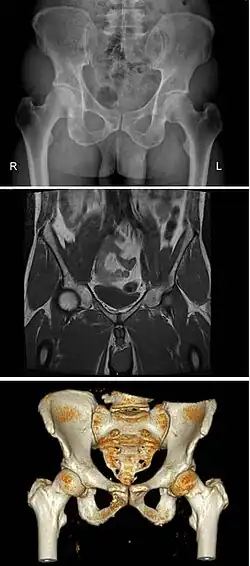

Variation

Modern humans are to a large extent characterized by bipedal locomotion and large brains. Because the pelvis is vital to both locomotion and childbirth, natural selection has been confronted by two conflicting demands: a wide birth canal and locomotion efficiency, a conflict referred to as the "obstetrical dilemma". The female pelvis, or gynecoid pelvis,[8] has evolved to its maximum width for childbirth—a wider pelvis would make women unable to walk. In contrast, human male pelvises are not constrained by the need to give birth and therefore are more optimized for bipedal locomotion.[9]

The principal differences between male and female true and false pelvis include:

- The female pelvis is larger and broader than the male pelvis which is taller, narrower, and more compact.[10] The female pelvis is lighter and thinner than the male pelvis.[11]

- The female inlet is larger and oval in shape, while the male sacral promontory projects further (i.e. the male inlet is more heart-shaped).[10]

- The sides of the male pelvis converge from the inlet to the outlet, whereas the sides of the female pelvis are wider apart.[12]

- The angle between the inferior pubic rami is acute (70 degrees) in men, but obtuse (90–100 degrees) in women. Accordingly, the angle is called subpubic angle in men and pubic arch in women.[10] Additionally, the bones forming the angle/arch are more concave in females but straight in males.[13]

- The distance between the ischia bones is small in males, making the outlet narrow, but large in females, who have a relatively large outlet. The ischial spines and tuberosities are heavier and project farther into the pelvic cavity in males. The greater sciatic notch is wider in females.[13]

- The iliac crests are higher and more pronounced in males, making the male false pelvis deeper and more narrow than in females.[13]

- The male sacrum is long, narrow, more straight, and has a pronounced sacral promontory. The female sacrum is shorter, wider, more curved posteriorly, and has a less pronounced promontory.[13]

- The acetabula are wider apart in females than in males.[13] In males, the acetabulum faces more laterally, while it faces more anteriorly in females. Consequently, when males walk the leg can move forwards and backwards in a single plane. In females, the leg must swing forward and inward, from where the pivoting head of the femur moves the leg back in another plane. This change in the angle of the femoral head gives the female gait its characteristic (i.e. swinging of hips).[14]